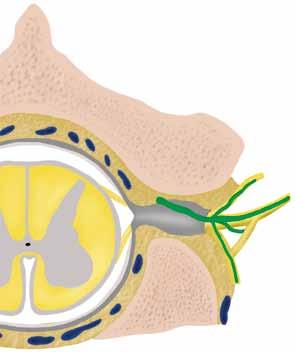

Tato bariéra se skládá – z pohledu od cévního lumen – z následujících vrstev: z endotelu, jeho bazální membrány, svalové vrstvy (u prekapilár), perivaskulární vazivové tkáně, bazální membrány epitelu a jednovrstevného epitelu thymu (► obr. 1.6 b, c). Endotel krevních cév ve dřeni thymu, zejména endotel postkapilárních venul, je naproti tomu propustný pro velké molekuly a buňky. Proto zde mohou antigeny z krve vstoupit do kontaktu s thymocyty (► obr. 1.6 a).

Obr. 1.6 Bariéra krev–thymus: a struktura bariéry krev–thymus; b–c vrstvy bariéry krev–thymus v průřezu: b kapilární oblast; c oblast arteriol. 1 Arterie; 2 pouzdro laloku z pojivové tkáně; 3 bazální lamina; 4 epitelová hraniční zóna; 5 epitelové retikulum; 6 venuly; 7 perivaskulární mezery; 8 endotel krevní kapiláry; 9 bazální lamina; 10 perivaskulární pojivová tkáň; 11 bazální lamina epitelové hraniční vrstvy; 12 epitelová hraniční vrstva; 13 endotel arterioly; 14 svalová vrstva. [L 134]